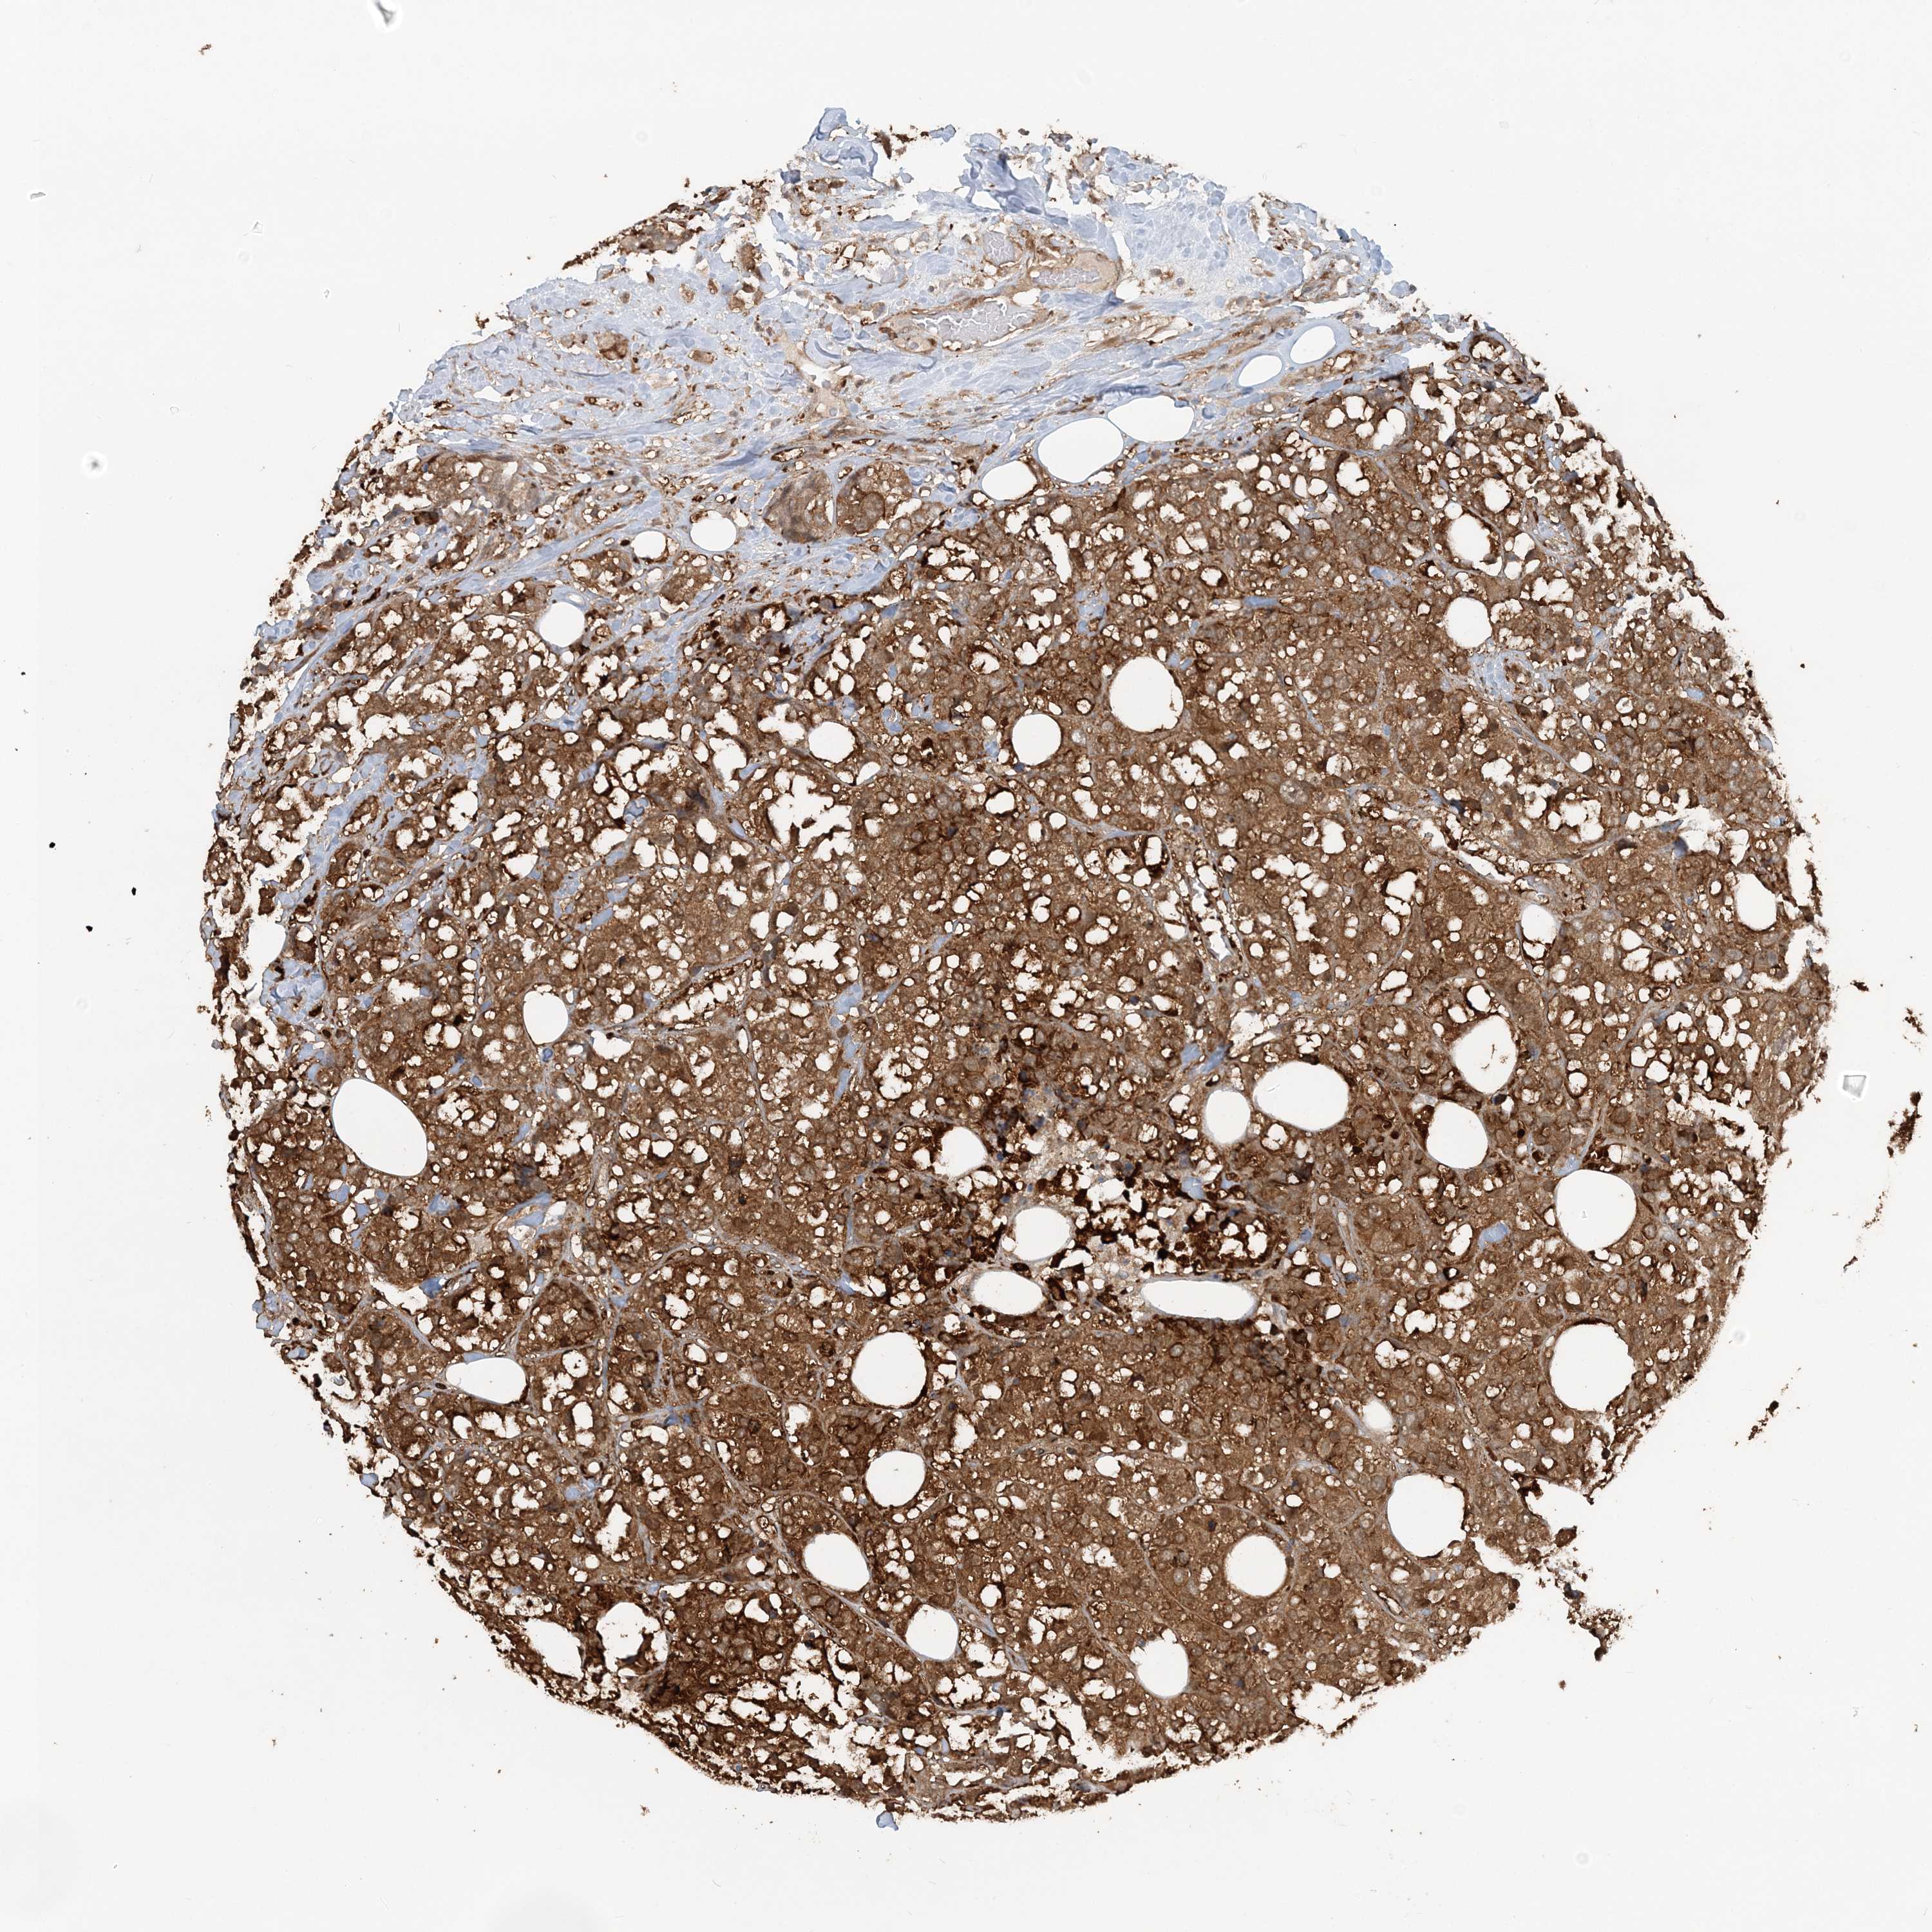

CANCER BREAST CANCER Show tissue menu

BRCA TCGA BRCA VALIDATION PROTEIN EXPRESSION